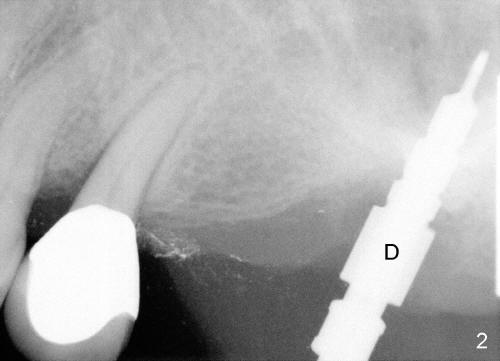

Mr. Tsang has a loose bridge (Fig.1: #13-15). The affected tooth (#15) was extracted two months ago. Immediate implant was placed (Fig.2: 4.5x17 mm tapered drill; Fig.3: 7x17 mm implant). It appears that the implant at the site of #15 must be somewhat parallel to the tooth #13, according to the trajectory of the drill in Fig.2.